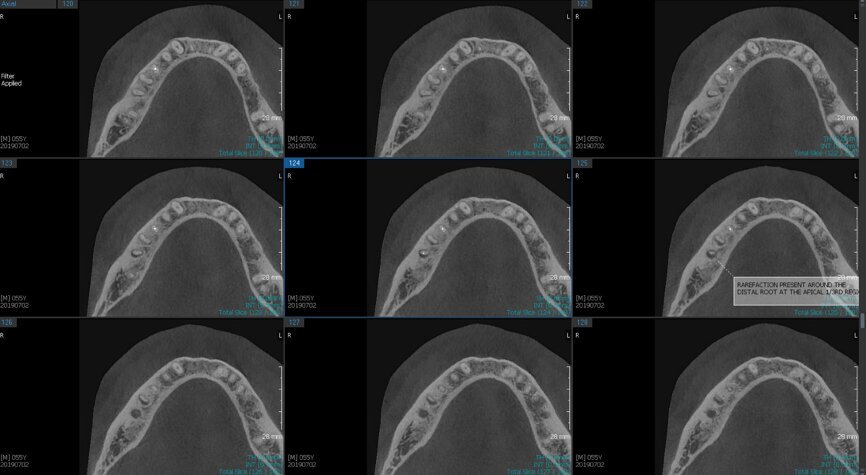

Fig.2a: Pre-op CBCT images of tooth #46: No obturation material in the distal and mesiobuccal canal (a); scanty obturation of the canals and breach of the floor of the pulp chamber, no obturation beyond a few millimetres down the orifice (b & c); radiolucency in the furcation area and periapical region of both roots (d -g).

Fig.2b: Pre-op CBCT images of tooth #46: No obturation material in the distal and mesiobuccal canal (a); scanty obturation of the canals and breach of the floor of the pulp chamber, no obturation beyond a few millimetres down the orifice (b & c); radiolucency in the furcation area and periapical region of both roots (d -g).

Fig.2c: Pre-op CBCT images of tooth #46: No obturation material in the distal and mesiobuccal canal (a); scanty obturation of the canals and breach of the floor of the pulp chamber, no obturation beyond a few millimetres down the orifice (b & c); radiolucency in the furcation area and periapical region of both roots (d -g).

Fig.2d: Pre-op CBCT images of tooth #46: No obturation material in the distal and mesiobuccal canal (a); scanty obturation of the canals and breach of the floor of the pulp chamber, no obturation beyond a few millimetres down the orifice (b & c); radiolucency in the furcation area and periapical region of both roots (d -g).

Fig.2e: Pre-op CBCT images of tooth #46: No obturation material in the distal and mesiobuccal canal (a); scanty obturation of the canals and breach of the floor of the pulp chamber, no obturation beyond a few millimetres down the orifice (b & c); radiolucency in the furcation area and periapical region of both roots (d -g).

Fig.2f: Pre-op CBCT images of tooth #46: No obturation material in the distal and mesiobuccal canal (a); scanty obturation of the canals and breach of the floor of the pulp chamber, no obturation beyond a few millimetres down the orifice (b & c); radiolucency in the furcation area and periapical region of both roots (d -g).

Fig.2g: Pre-op CBCT images of tooth #46: No obturation material in the distal and mesiobuccal canal (a); scanty obturation of the canals and breach of the floor of the pulp chamber, no obturation beyond a few millimetres down the orifice (b & c); radiolucency in the furcation area and periapical region of both roots (d -g).

When I had a close look at the preoperative radiograph from the referring dentist (Fig. 1a), I observed that there was insufficient obturation of the mesial canals and almost no obturation of the distal canal. Both roots displayed periapical radiolucency. The clinical examination revealed a Grade I mobility, and the tooth was tender to percussion. The periodontal examination ruled out any pockets and loss of attachment. We took an intra-oral periapical radiograph (Fig. 1b), from which we observed the loss of coronal structure and a large radiolucent area over the furcation area and the periapical area of both the mesial and the distal roots. A CBCT scan of tooth #46 was advised to check for any details that may have been missed in the intra-oral periapical radiograph (Figs. 2a–g). From the CBCT scan, it could be observed that there was inadequate obturation of the distal canal on the horizontal plane, no obturation beyond the middle third in the mesial canals and a breach of the floor of the pulp chamber. The questionable prognosis was explainedto the patient, and written consent was obtained.